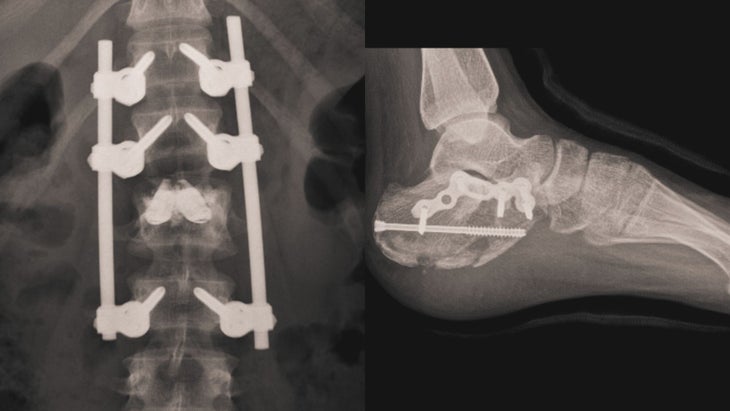

After a short ambulance ride to a nearby Geneva hospital, Hôpitaux Universitaires de Genève, Al Qunaibet got her diagnosis: Fractures in both feet and two broken vertebrae in her back.

The doctors performed surgery on both her left foot and her back, leaving metal rods inserted into both to help stabilize the broken bones. According to Al Qunaibet, the Saudi embassy in Switzerland stepped in and covered all costs.